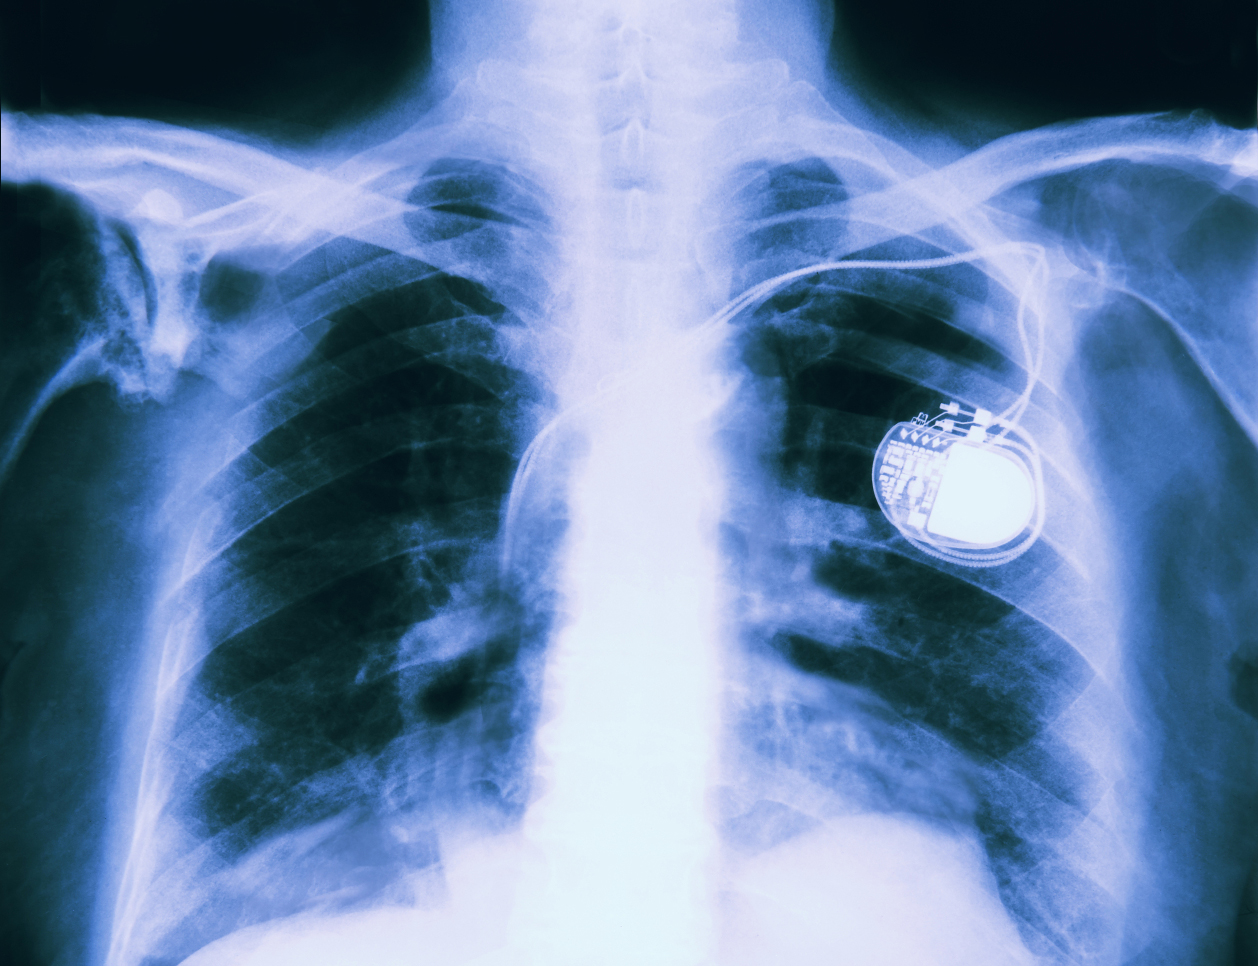

Cory Doctorow for the Electronic Frontier Foundation: As networked computers disappear into our bodies, working their way into hearing aids, pacemakers and prostheses, information security has never been more urgent — or personal. A networked body needs its computers to work well and fail even better.

But a profit motive that might conflict with users’ best interests isn’t the worst problem. The great danger is safety. Medical implants are increasingly equipped with wireless interfaces, because they’re cheap and it’s hard to attach a USB cable to a device that has been implanted in your chest cavity.

That means that bugs in medical implants can be exploited over their wireless interfaces, too. For example: lethal shocks from implanted pacemakers and defibrillators. It was not for nothing that former Vice President Dick Cheney had the wireless interface on his pacemaker deactivated.

However you feel about copyright law, everyone should be able to agree that copyright shouldn’t get in the way of testing the software in your hearing aid, pacemaker, insulin pump or prosthetic limb to look for safety risks — or privacy risks, for that matter. Implantees need to know the truth about the reliability of the technology they trust their lives to.